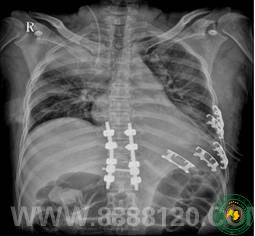

360°减压复位融合技术创造手术辉煌

360°减压复位融合技术创造手术辉煌6495

宜宾市第二人民医院 图文